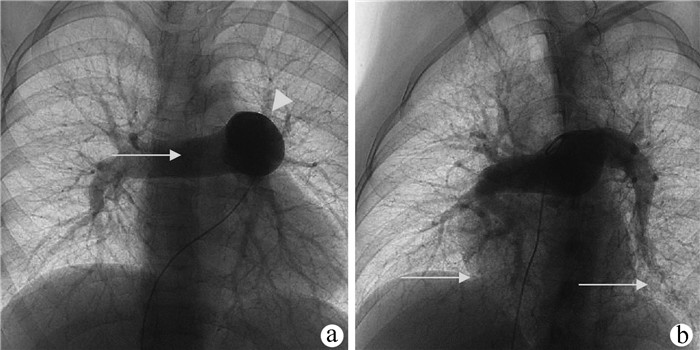

Advances and challenges in clinical research on hepatic hydrothorax

Bo MA, Tianling SHANG, Jianjie HUANG, Zhixin TU, Yan WANG, Yujin HAN, Xiaoyu WEN, Qinglong JIN

2022, 38(2): 452-456. DOI: 10.3969/j.issn.1001-5256.2022.02.040

Abstract(1343) HTML (467) PDF (1934KB)(106)

Abstract:

Hepatic hydrothorax (HH) is a challenging complication of liver cirrhosis associated with portal hypertension, and its pathogenesis and therapeutic measures remain unknown. This article summarizes and reviews the advances and challenges in the research on the pathogenesis, clinical manifestations, diagnosis, and treatment of HH and proposes a multidisciplinary treatment strategy, including reducing the production of ascites, preventing effusion from entering the thoracic cavity, removing pleural effusion, occluding the pleural cavity, and performing liver transplantation, so as to provide a reference for more clinicians.